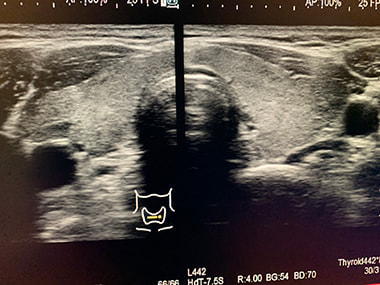

甲状腺エコー検査:

甲状腺の大きさ・腫瘍(のう胞・腺腫・がん)の有無などを調べます。

炎症・良性悪性腫瘍の診断に役立ちます。